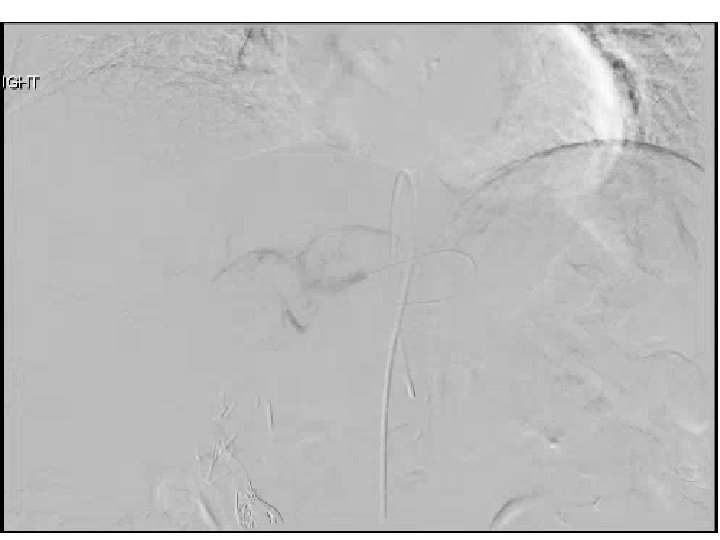

SIRT

Embolization of massive arteriovenous shunts in HCC • Etiology thought secondary to hepatic vein

Embolization of massive arteriovenous shunts in HCC • Etiology thought secondary to hepatic vein invasion (micro/macro) by tumor with aberrant angiogenesis causing arterio-venous connections • Case reports describe either temporary occlusion of hepatic vein during TACE or permanent occlusion with either AVP or coils